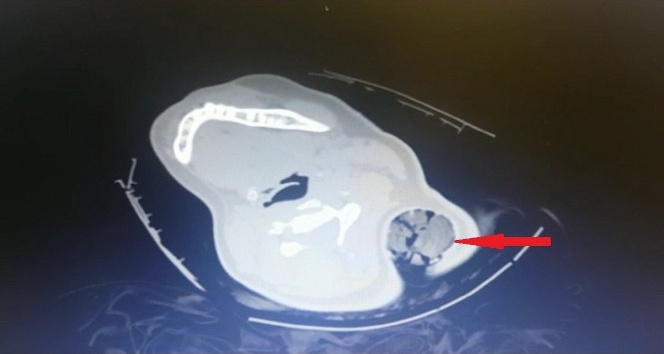

Pazarcık ilçesinde meydana gelen trafik kazasında 19 yaşındaki B.Ö.’nün boynuna 30 santim uzunluğunda tahta parçası saplandı. Boynundan giren ve koltuk altından görülen tahta parçasıyla Kahramanmaraş Sütçü İmam Üniversitesi (KSÜ) Sağlık Uygulama ve Araştırma Hastanesinde kaldırılan genç kız acil ameliyata alındı.

Yaklaşık yarım saat süren ameliyat sonrası çıkarılan tahta parçasının inanılmaz bir şekilde sinir ve damarlara zarar vermemesi neticesinde genç kız, tedavisinin tamamlanmasının ardından taburcu edildi.

Tahta kazığı ameliyatla çıkaran KSÜ Tıp Fakültesi Ortopedi ve Travmatoloji Anabilim Dalı Öğretim Üyesi Dr. Bülent Güneri, genç kızın sadece bir kaburgasının kırıldığını, sinir ve damarlarının zarar görmediğini belirterek, "Tıp literatüründe bu şekilde boyundan girip koltuk altından çıkan bir cisim yok. Hastayı acil ameliyata aldık. Ameliyat esnasında Göğüs Cerrahisi hocamız Dr. Öğretim Üyesi Ahmet Acıpayam ve Kalp ve Damar Cerrahisi hocamız Doç. Dr. Mehmet Acıpayam hazır bulundular herhangi bir komplikasyona yönelik olarak. Ameliyathanede yaptığımız değerlendirmeden sonra anestezi altında yaklaşık 30 santimetrelik tahta bir kazık çıkardık hastadan. Kazık, hastanın saçlarını dolayarak boynundan girip sol kol altından çıkmıştı. Ve böyle kirli bir yaralanma, ev dışında, sokakta olan bir yaralanma enfeksiyon açısından oldukça risklidir. Ama ameliyat esnasında yaptığımız girişimler ve titizlikle uyguladığımız antibiyotik tedavisi sayesinde hastamızda bir enfeksiyon meydana gelmedi” dedi.

“Tıp literatüründe benzer yaralanmalar var, metal ve tahta cisim saplanmaları görülüyor. Ancak bu şekilde boyundan girip koltuk altından çıkan bir cisim yaptığım taramalarda tespit etmedim. Ancak literatürde bildirilen vakalarda çok ciddi sinir yaralanmaları ya da omuriliğe saplanıp da enfeksiyona yol açan bu nedenle tedavi görmek zorunda olan hastalar mevcut. Bizim hastamızda herhangi sinir veya damarsal yapıya denk gelmedi ancak bir kaburga kırığına yol açtı ve içeride bol miktarda hastanın saç bulunduğu için bizi daha çok uğraştıran içeride bulunan saç parçalarıydı. Biz, kazığın gidiş yönü boyunca açmayıp, kazığı ters yönde çıkartıp içeriye bol miktarda steril sıvıyla yıkama uyguladık ve iyi bir antibiyotik tedavisi verdiğimizi düşünüyorum. Bu sayede de bir sorun meydana gelmedi. Hasta oldukça talihli bence. Beni ve ekibimi oldukça şaşırttı. Ve hastayı birlikte değerlendiren cerrahi branştan diğer hocalarımızı da oldukça şaşırttı. Adeta mucize gibiydi diyebilirim.”